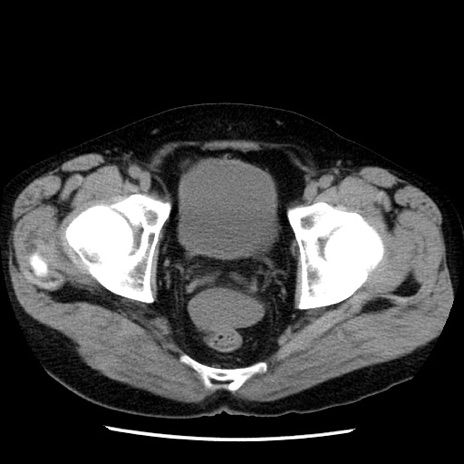

症例29(横断像)

【症例】40歳代男性

【現病歴】2日前から胃痛あり。徐々に周期的な激痛に変化した。本日になっても激痛があるため受診。

【身体所見】意識清明、BT 38-39℃台あり、腹部:膨満、やや硬、右下腹部に圧痛あり。

【データ】WBC 8500、CRP 23.26